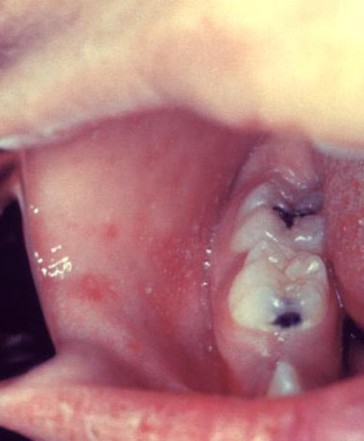

• 2 days later, white spots (Koplik spots) appear inside the mouth.

White Koplik spots and redness of the inside of cheek.(Below)

White Koplik spots